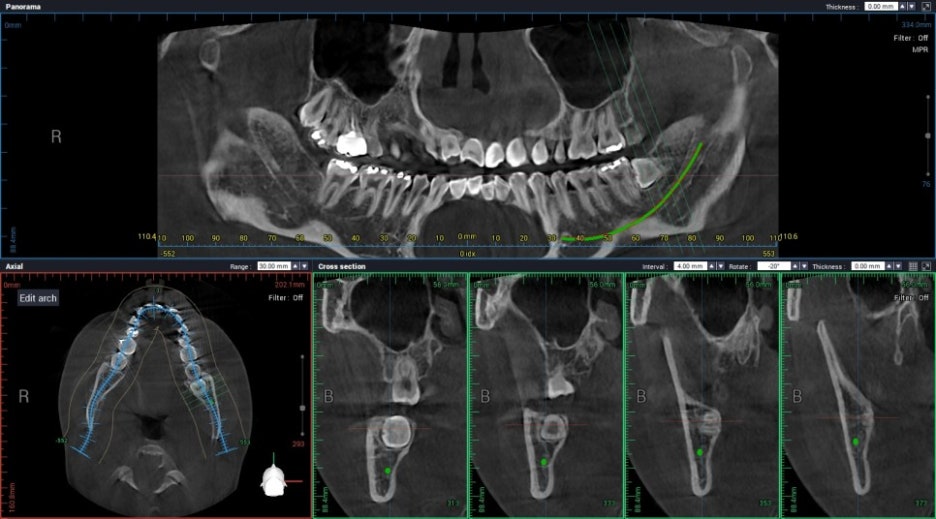

사랑니가 깊게 매복되었거나, 임플란트 수술이 계획된 환자에서 촬영하는

"치과용 CT" 입니다. 30 μSv 정도 방사선이 인체에 흡수됩니다.

파노라마 3장 촬영하는 수준입니다.